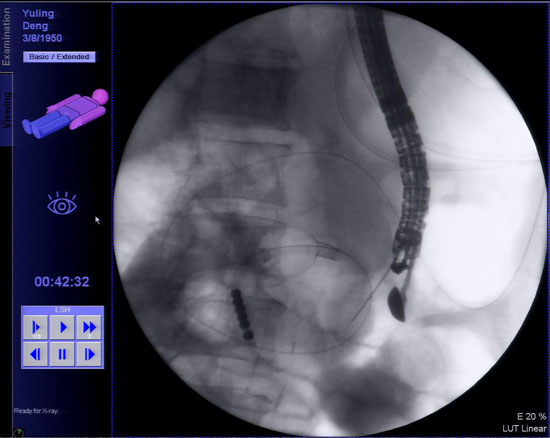

经过术前准备,3月7日下午患者被送入内镜诊疗中心,术中在X线透视下胡锦华副主任医师将双球囊送入空肠固定屈氏韧带附近肠管,在超声内镜引导下经胃腔穿刺肠壁置入导丝,沿导丝放置双蘑菇头支架从而实现胃空肠吻合。术中X线透视下多次造影,证实连接胃腔与肠腔的支架通畅、无渗漏,手术取得成功。术后患者略感腹胀,未再出现其他不适症状。

超声内镜引导下经胃穿刺空肠